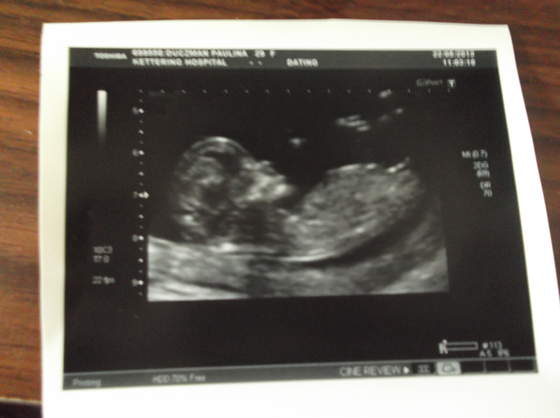

dla mnie dwójka to zawsze było minimum ale też taki max ;-) ciesze się że jesteś zadowolona ze scanu śliczny dzidziuś :-)